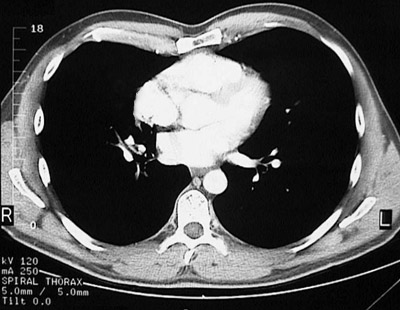

[T8] This is a normal chest CT scan demonstrating the right lung and left lung and pectoralis major muscle and right atrium and right ventricle and left atrium and left ventricle and aortic root and sternum and descending aorta and azygous vein and esophagus and serratus anterior muscle and latissimus dorsi muscle and scapula and rhomboid major muscle and trapezius muscle and sacrospinalis muscle and transversospinal muscle in the upper chest.